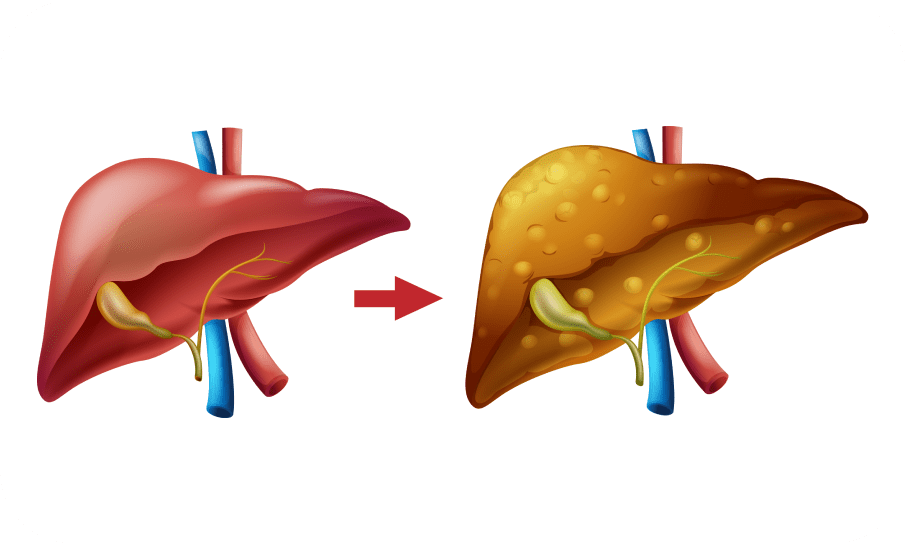

Картинки с надписью Liver: Как выбрать и использовать